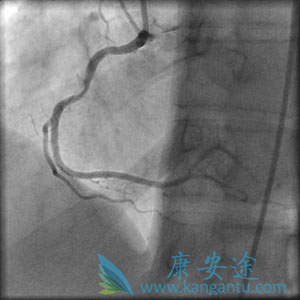

血管成形术和支架通常作为治疗稳定性心绞痛或紧急作为心脏病发作后的突发程序,以打开突然阻塞的动脉(下图)。

在心脏病发作(标签和箭头)和右侧,在“主要”血管成形术和支架之后阻塞血液超过阻塞的左前降支动脉,血管外流动性好